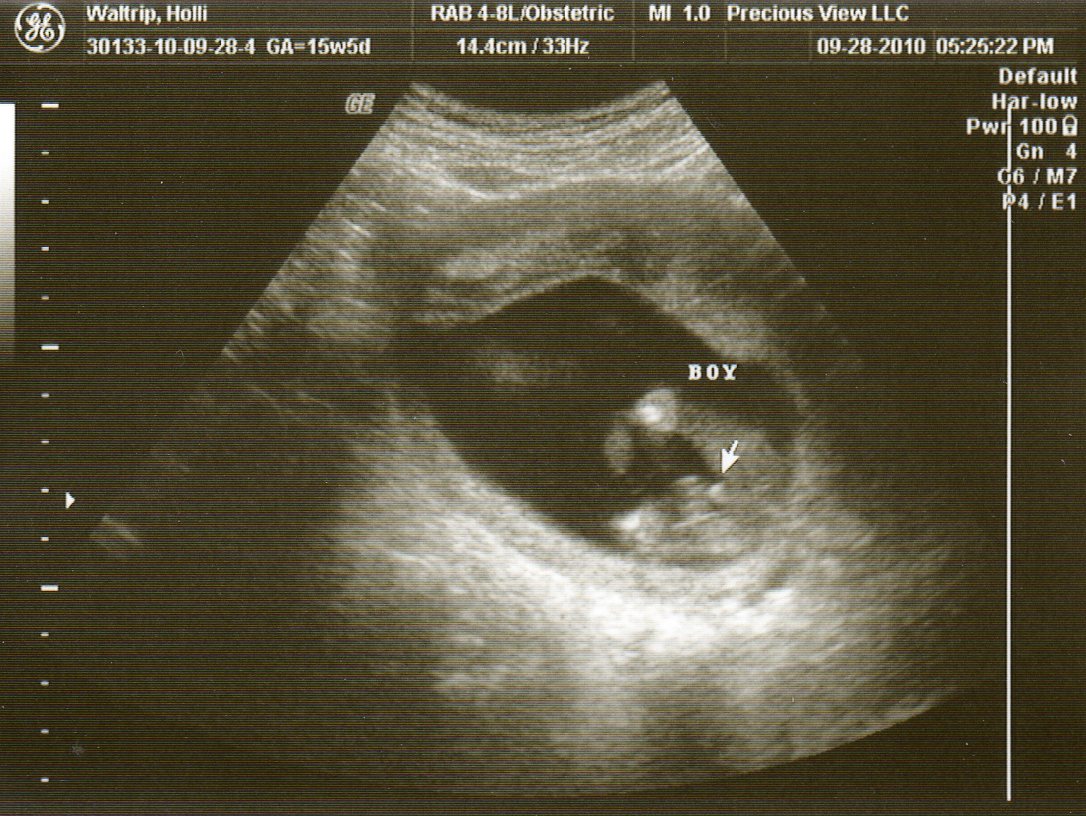

Because of this, my doctor scheduled me to have another ultrasound yesterday (at my 24 week appointment) to try to get a view of the things we couldn't see last time. It took about 10 seconds for the lady to say something like "Well, the baby just doesn't want me to see what I need to see." She said he was sitting with his bottom down, looking face forward AGAIN. As soon as she turned the screen around, this is what we saw...

Looks very familiar don't you think?  Needless to say, I was very excited when she and my doctor told me we get to have ANOTHER ultrasound at my 28 week appointment!  He wants to try again to get those shots that he hasn't been able to get yet.  I was trying to figure it up today, and I think we've gotten to have a total of 9 ultrasounds so far.  Don't get me wrong, I am definitely not complaining.  We love seeing our little guy every few weeks, and I've decided he just likes having his picture taken.  :)

We also got to see his nostrils, lips (of course he was moving his mouth...eating I guess), and his boy parts.